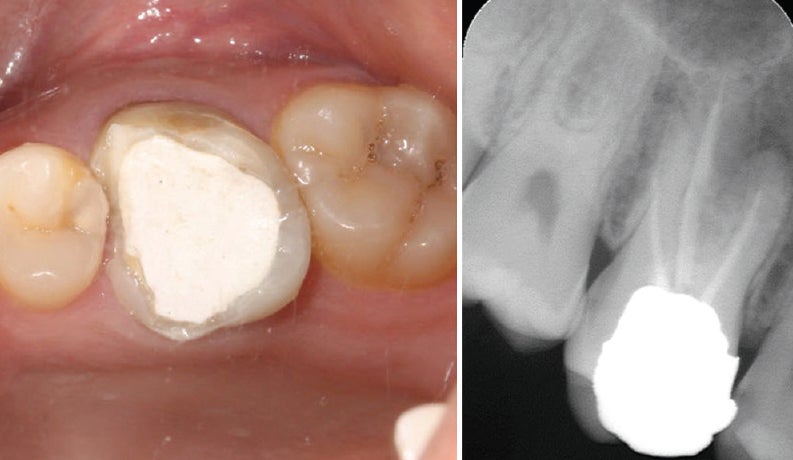

신경치료 후 치아는 내부 구조가 약해져 쉽게 깨질 수 있습니다. 크라운은 이를 보호하고, 씹는 기능과 심미성을 복원해주는 중요한 치료 단계로, 선택이 아닌 필수입니다.

크라운은 손상된 치아 위를 씌우는 인공 보철물로, 치아를 외부 충격에서 보호하고 정상 기능과 자연 외형을 회복시켜 줍니다. 어금니는 내구성, 앞니는 심미성을 고려해 재료를 선택하는 것이 핵심입니다.

1. 치과 신경치료란?신경치료(근관치료)는 치아 내부의 손상된 신경(치수)을 제거하고, 그 공간을 소독한 후 밀봉하여 감염을 막는 치료입니다. 충치가 깊어져 신경까지 침범하거나 외상, 감염